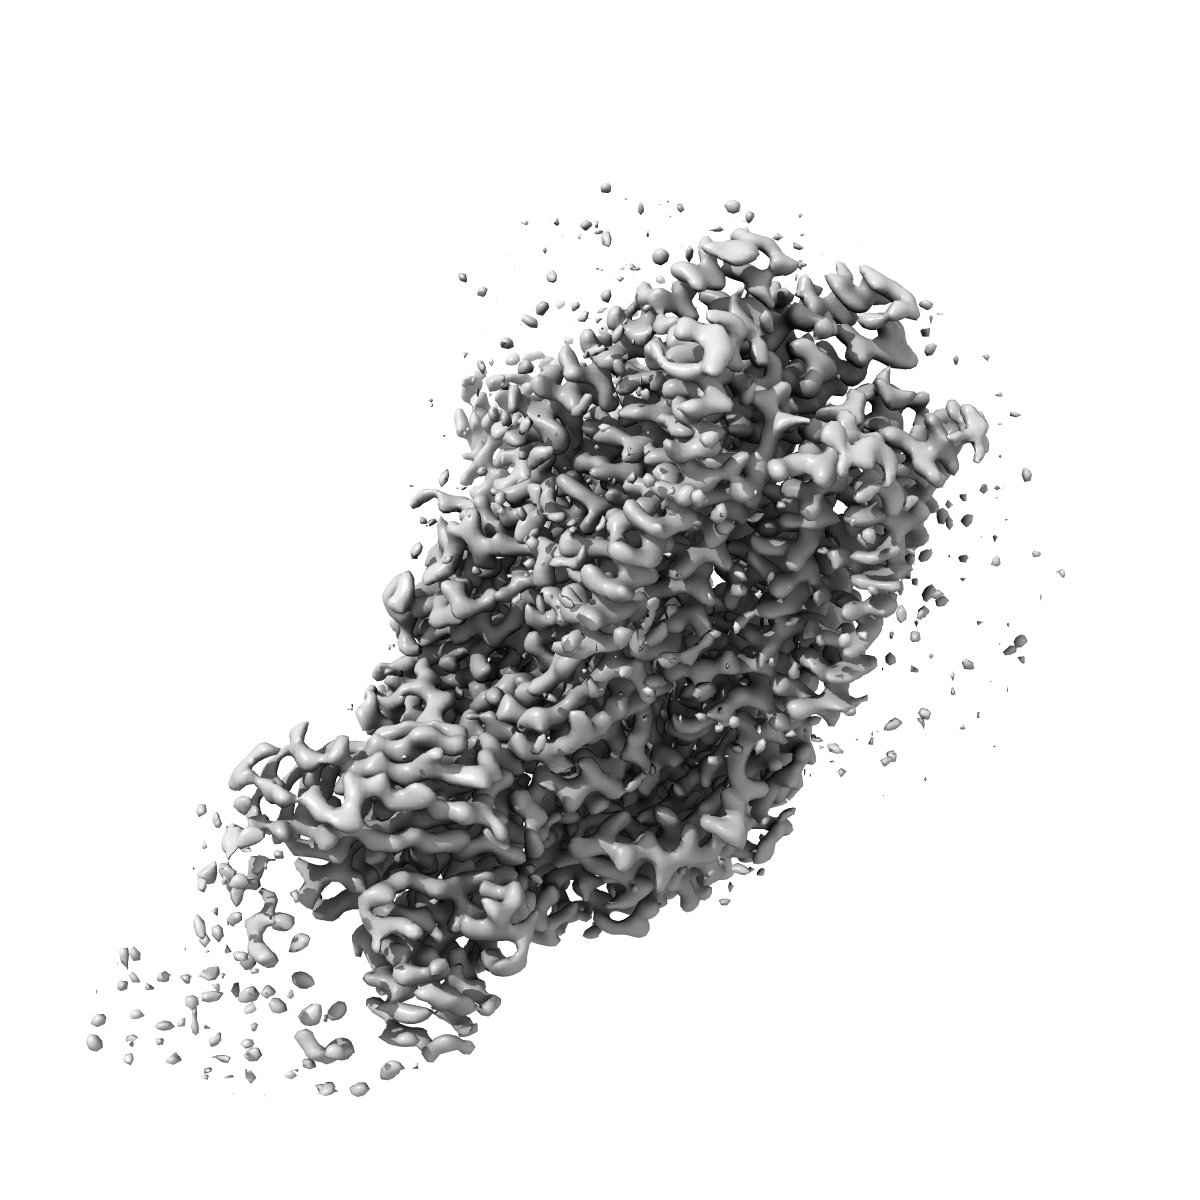

EMD-22034

Human GABAA receptor alpha1-beta2-gamma2 subtype in complex with GABA plus etomidate

Sample: Human GABA-A receptor alpha1-beta2-gamma2 subtype in complex with GABA and etomidate

Fitted models: 6x3v

Shared structural mechanisms of general anaesthetics and benzodiazepines.

Kim JJ, Gharpure A , Teng J, Zhuang Y , Howard RJ , Zhu S, Noviello CM, Walsh Jr RM , Lindahl E, Hibbs RE

(2020) Nature , 585 , 303 - 308